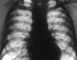

Идиопатический гемосидероз лёгких (эссенциальный легочный гемосидероз) встречается, как правило, у детей и характеризуется множественными повторными кровоизлияниями в легочную ткань. Проявляется легочными кровотечениями различной степени. Во время обострений могут наблюдаться умеренная лихорадка, боли в груди, увеличение печени и селезенки, в мокроте обнаруживают гемосидерофаги. Рентгенологически выявляются пятнистые тени (воспалительные инфильтраты) преимущественно в нижних отделах Л. , а в период ремиссий — мелкие мономорфные очаговые тени, обусловленные отложением гемосидерина; при длительном течении заболевания определяется мелкосетчатая диффузная деформация легочного рисунка, обусловленная уплотнением интерстициальной ткани (рис. 12). Лечение главным образом симптоматическое (при легочных кровотечениях проводят гемостатическую и кровезаместительную терапию). Некоторые авторы рекомендуют глюкокортикостероиды, плазмаферез, спленэктомию.